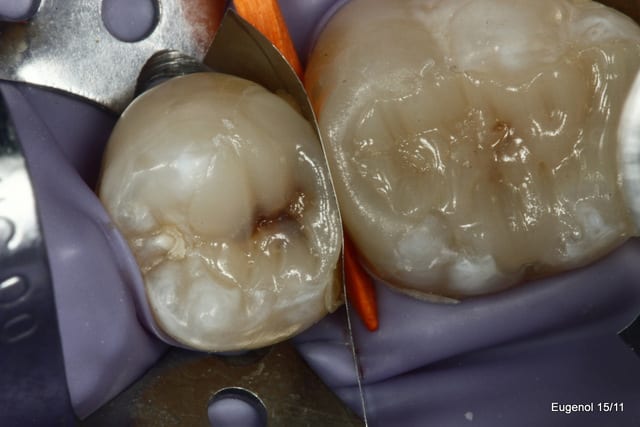

Ben les photos finales c'est après réglage de l'occlusion sinon c'est pas drôle.

Quand on s'appuie sur les cuspides restantes et qu'on donne une morphologie assez naturelle, en général il y a peu de retouche occlusale.

Sinon je fais les sillons secondaire a la sonde.

C'est du compo Enamel HRI en dentine et Esthelite en email qui se sculpte facilement et reste pourtant souple et autolissant...

Le polissage c'est des brossettes chargées en silice, et avec de la pâte à polir.